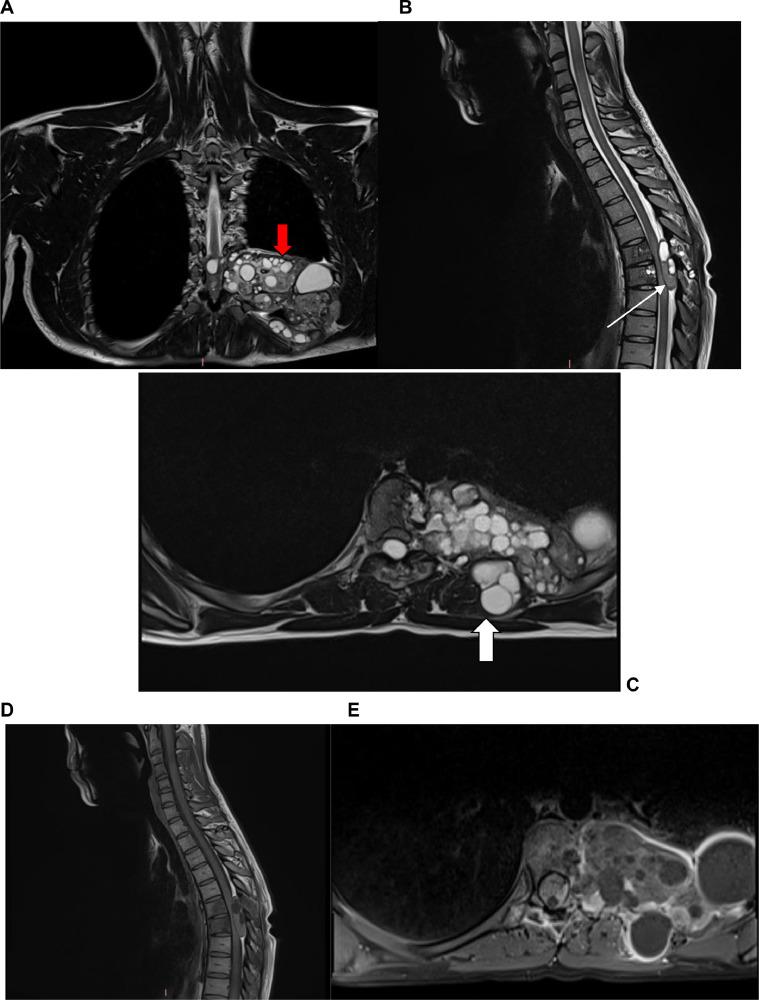

Hydatid cyst is a well-known pathology today. Although uncommon in Western countries, it remains endemic in countries with a strong livestock culture. It is caused by , whose larval form develops in herbivores, primarily sheep, before infecting dogs. Humans, however, are considered accidental hosts. In the vast majority of cases, the liver and then the lungs are affected, but any organ can be involved, leading to atypical locations. Here, we present the case of a 32-year-old female patient who presented with a clinical picture of back pain and slow spinal cord compression. Imaging revealed a 12 cm polycystic dorsal costovertebral mass compressing the spinal cord. A decompressive laminectomy was performed, resulting in a reduction of spasticity.

包虫囊肿如今是一种广为人知的病理学疾病。尽管在西方国家并不常见,但在有着浓厚畜牧文化的国家中仍属地方病。它由[某种寄生虫]引起,其幼虫形式在食草动物,主要是绵羊体内发育,之后感染犬类。然而,人类被视为意外宿主。在绝大多数情况下,肝脏继而肺部会受到影响,但任何器官都可能受累,导致出现非典型部位。在此,我们报告一例32岁女性患者,其临床表现为背痛和脊髓缓慢受压。影像学检查显示一个12厘米的多囊性背侧肋椎肿块压迫脊髓。实施了减压性椎板切除术,痉挛症状有所减轻。